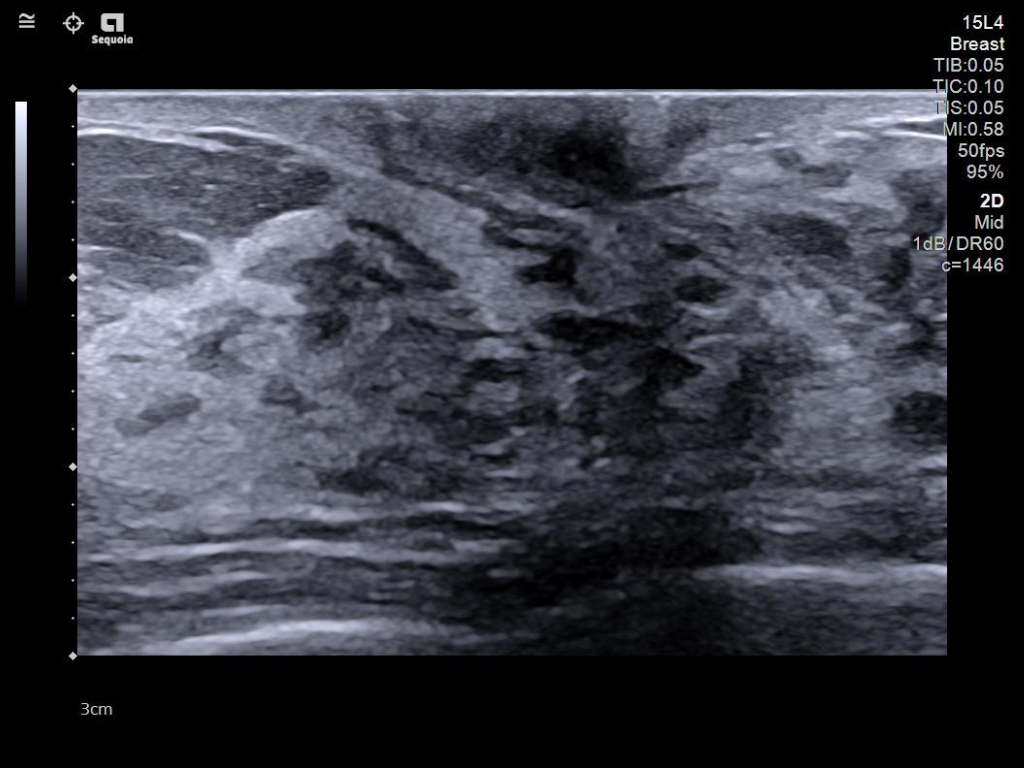

The latest updates on ACUSON Sequoia use the power of groundbreaking AI for abdominal cases, includes advanced breast visualization to deliver new levels of image quality confidence, and tackles the toughest challenges in musculoskeletal imaging, all while saving your team from needless strain and pain.

A clearer, deeper perspective with optimal acoustics for each clinical use case. Expand your assessment with advanced tools that take ultrasound beyond its traditional role.

- Next Gen 2D-SWE for greater sensitivity in detection and visualization of malignant breast lesions.